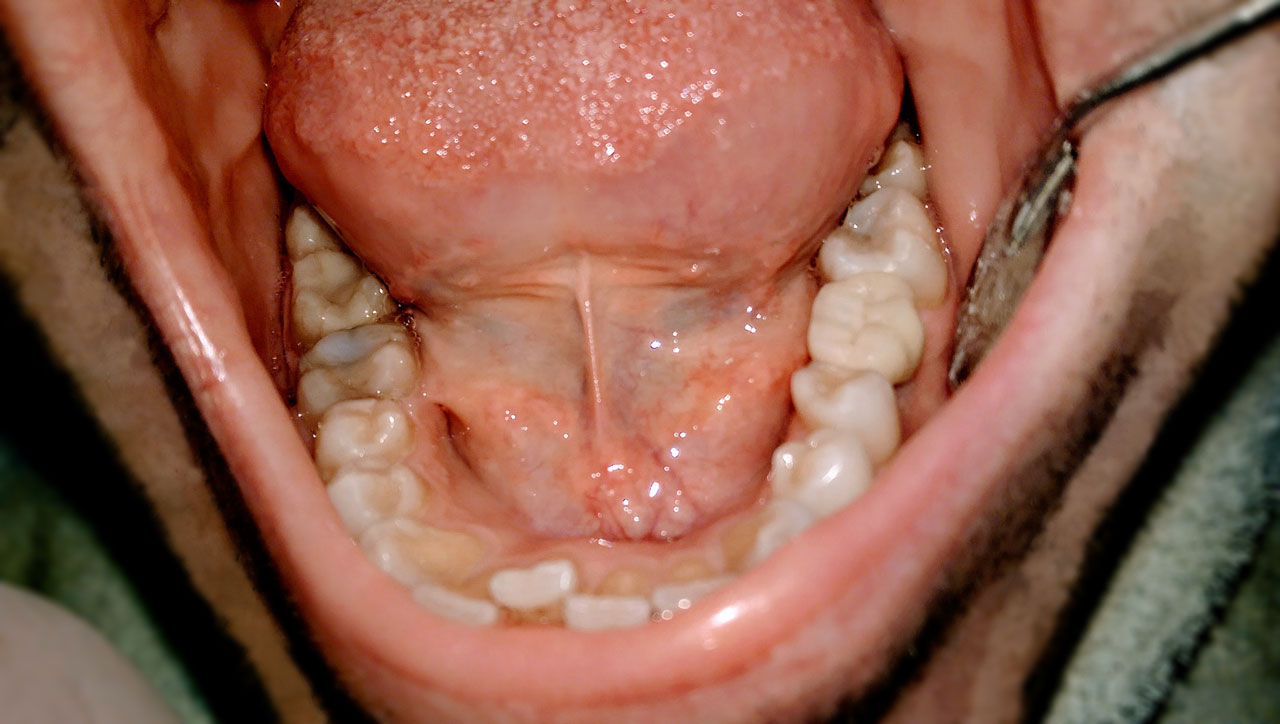

Elhanyagolt fogsor cseréje 2 nap alatt

2 nap alatt varázsoltuk ezt a szép esztétikus alsó, felső körhídat implantátumokkal megtámasztva a korábban elhanyagolt szájba. Az 1. nap 26 fogat távolítottunk el, mert annyira rossz állapotban voltak, és rögtön azonnal terhelhető IHDE svájci implantátumokat raktunk be, fentre 8, lentre 6 darabot. A sebeket összevarrtuk és intraorális szkennerrel digitális lenyomatot vettünk. 2 nap múlva pedig beragasztottuk a kész PMMA műanyag körhidakat. Dr. Kelemen Péter és a Symbion Fogtechnika munkája.